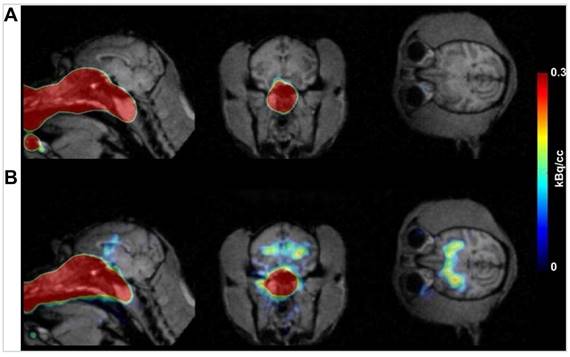

Diazepam-loaded poly (lactic-co-glycolic acid; PLGA) NPs have been assessed in rats for efficiently delivering drugs directly to the brain intranasally. Each rat received 20 μL of the radiolabelled formulation, administered intranasally using a micropipette, with 10 μL of [99mTc]diazepam solution and 10 μL of diazepam-NP administered in each nostril [36]. The developed PLGA NPs (diazepam-NP) are nanoscale particles, and the spray droplets themselves are NPs. Gamma scintigraphy allowed for the visualisation and quantification of [99mTc]diazepam-NP biodistribution, with a pronounced increase in radioactivity seen in the rat brain at 0.5 h post-IN administration, which demonstrated the superior uptake of [99mTc]diazepam-NP via IN administration (e.g., 1.35 at 0.5 h), compared to [99mTc]diazepam solution via both IV injection and IN administration (see Figure 3). Furthermore, biodistribution studies undertaken 8 h post-administration allowed tracking of drug persistence in the brain. The brain/blood ratio of the drug was highest for [99mTc]diazepam-NP with IN administration across all the measured time points, underlining the potential of this route in maintaining a sustained drug presence in the brain. The NPs provided better DTE% and DTP%, with values of 258 and ~61, respectively. This important finding confirmed effective nose-to-brain transport of diazepam facilitated by a solution of PLGA-NPs, in rats. The active agents, in this case, diazepam, are encapsulated within these NPs, ensuring controlled release and targeted delivery to the brain.

Figure 3

Gamma scintigraphy images of rats 30 min post-administration/injection. A: [99mTc]diazepam solution post-IV injection. B: [99mTc]diazepam solution post-IN administration. C: [99mTc]diazepam-NP post-IN administration. Redrawn from [36]. [created with BioRender.com].